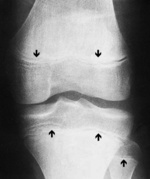

Aspekt ortopedyczny. Okres dorastania jest uwarunkowany prawidłową czynnością chrząstek wzrostowych, które są najbardziej czynne w okolicy kolana (dalsza nasada uda i bliższa nasada piszczeli) (ryc. 1). Od prawidłowej czynności chrząstek wzrostowych zależy wzrost i oś kończyny. Wzmożona czynność chrząstek wzrostowych przypada na 7.-15. r.ż. Bardzo często przeciążenia i przypadkowe urazy przyczyniają się do zmniejszenia aktywności chrząstek wzrostowych (niski wzrost), asymetrycznego zrastania (zaburzenie osi kończyny na poziomie stawu kolanowego) lub całkowitego przedwczesnego zarośnięcia (skrócenie kończyny). Ponadto należy wspomnieć, że nieprawidłowości rozwojowe okolicy stawu kolanowego na podłożu dysplastycznym ujawniają się dopiero właśnie w wieku szkolnym podczas zwiększonej aktywności fizycznej. Te nieprawidłowości to: wysokie ustawienie rzepki z tendencją do jej zwichnięcia, anomalie stawu rzepkowo-udowego, zaburzenia osi kończyny na poziomie stawu kolanowego (zwykle koślawe).